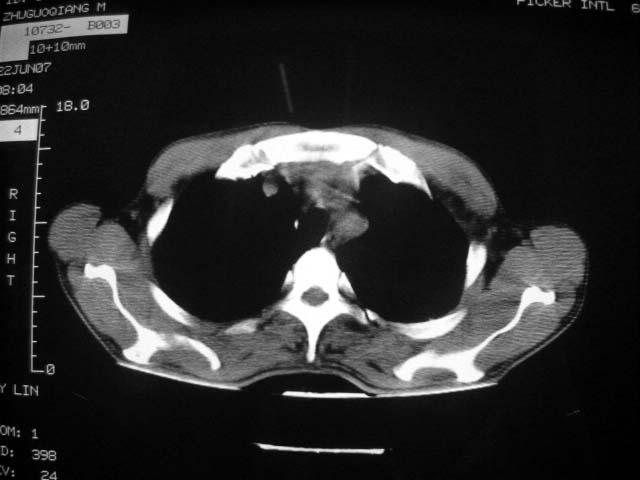

标题: CT7988D:近期图像 出乎意料!

从ct7988c 至今未用任何抗生素及抗痨药,维持保肝治疗。患者低热、咳血渐消失。

07年6月22号复查

前几次大家认为是转移癌,但此次复查病灶却明显吸收好转,不支持诊断。请大家讨论。[emb10]